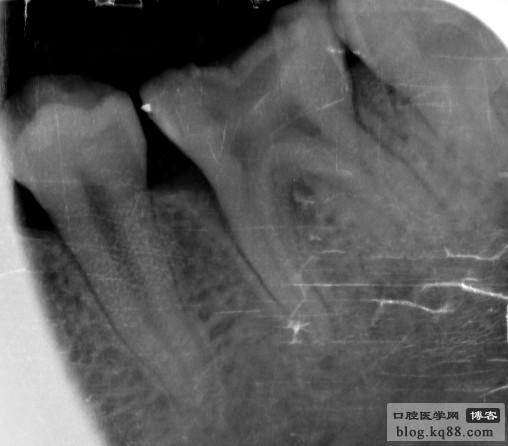

上頜中切牙及側(cè)切牙

左上中切牙

右下5

右上5、6

右下6

左上6

右下8

右上8